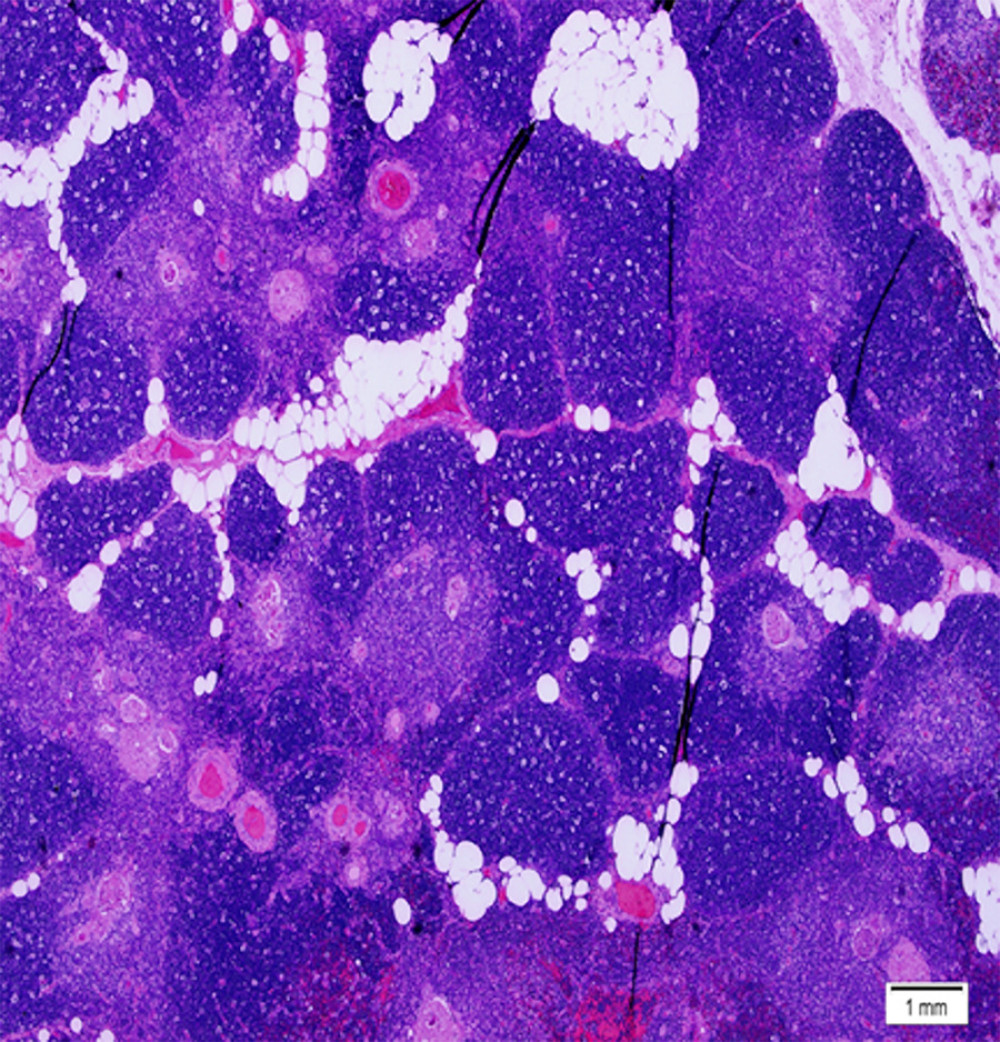

Low power view of a micronodular thymic carcinoma with Bcell Thymic Lymphosarcoma It is also known as mediastinal. There are currently four distinct forms of bls: Thymic lymphsarcoma is a malignant tumour that often metastasises. Thymic lymphosarcoma in a cow. Juvenile lymphosarcoma occurs most often in animals 6 months old. The trachea is seen on cross section at. Involvement of the lung is unusual. Cytologic examination of pleural fluid revealed an increased. Thymic Lymphosarcoma.

Microscopic images of thymic hyperplasia great lymphoid follicles ((a Thymic Lymphosarcoma It is also known as mediastinal. Ventral is down in this image; Thymic lymphoma, also known as adolescent lymphoma is extremely rare and most commonly occurs in cattle between six months and two. The trachea is seen on cross section at. Cytologic examination of pleural fluid revealed an increased number of atypical lymphocytes. Thymic lymphsarcoma is a malignant tumour that. Thymic Lymphosarcoma.

Microscopic appearance of micronodular thymoma with lymphoid stroma Thymic Lymphosarcoma Cytologic examination of pleural fluid revealed an increased number of atypical lymphocytes. It is also known as mediastinal. Calf form, thymic form, skin form, and adult or bovine leukemia virus (blv) associated form. Thymic lymphosarcoma in a cow. Ventral is down in this image; Juvenile lymphosarcoma occurs most often in animals 6 months old. The heifer died, and at necropsy,. Thymic Lymphosarcoma.

H&E stained sections. Islands of thymic tissue alternating with mature Thymic Lymphosarcoma Ventral is down in this image; Cytologic examination of pleural fluid revealed an increased number of atypical lymphocytes. The heifer died, and at necropsy, thymic and metastatic mammary. Juvenile lymphosarcoma occurs most often in animals 6 months old. Sporadic lymphosarcoma manifests in three main forms: There are currently four distinct forms of bls: Calf form, thymic form, skin form, and. Thymic Lymphosarcoma.